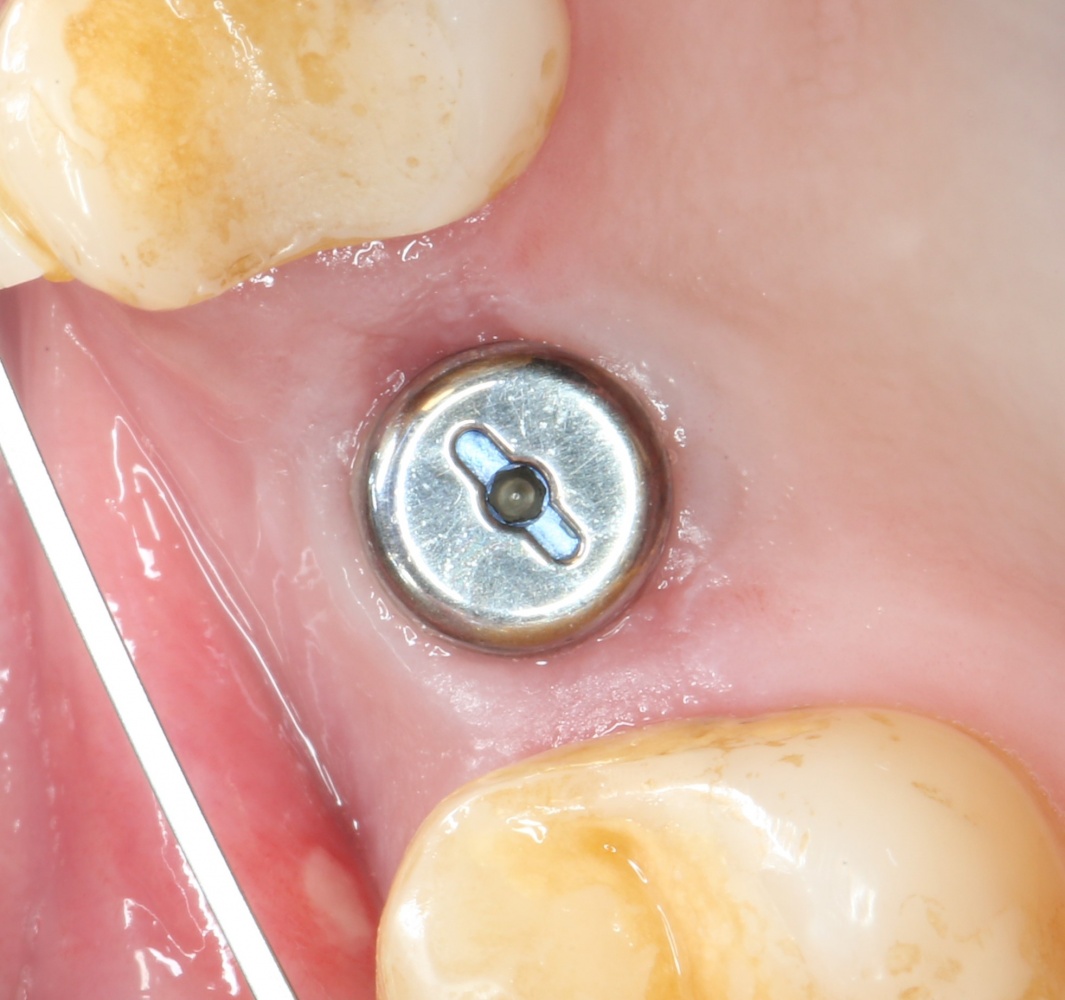

Однако, в этот раз я решил немного изменить план лекции. Теперь свою часть каждого из семинаров я буду посвящать какой-то конкретной операционной методике, рассказывая о ней чуть подробнее, чем принято говорить «бесплатно». И начнём мы с синуслифтинга, самой распространенной остеопластической операции в мире.

Каковы показания к открытому синуслифтингу? Когда его можно проводить совместно с установкой имплантов. а когда лучше сделать отдельным этапом?